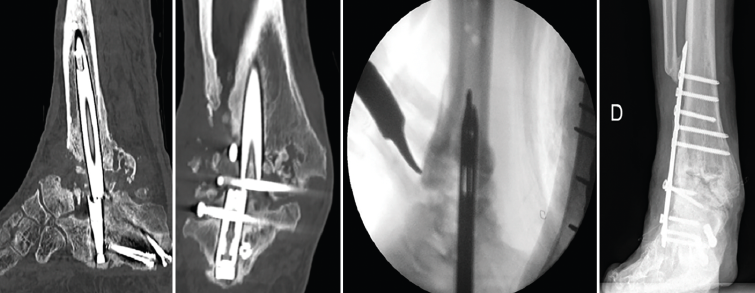

Figura 2. Agujas guías curvadas de revisión para la extracción de clavos rotos.

La reintervención se llevó a cabo a los 18 meses de la primera cirugía. En primer lugar, a través del punto de entrada plantar, se fijó el extremo distal del clavo con el sistema de extracción y se retiró el tornillo de bloqueo calcáneo. A continuación, se extrajo el tornillo proximal de la tibia y el astragalino extruido. Para la extracción del fragmento proximal del clavo, a través de la luz del clavo se introdujeron 2 guías con punta curvada, diseñadas para la extracción de los clavos de fémur rotos, enganchando la parte proximal del mismo y procediendo a su retirada (Figura 2). Se realizó un nuevo fresado del canal medular con el sistema RIA (reamer/irrigator/aspirator) (DePuy Synthes) y se colocó un clavo con una longitud y un diámetro mayores (210 y 13 mm, respectivamente). Mediante abordaje percutáneo se colocó el injerto en pasta ósea que obtuvimos con el sistema RIA a nivel tibiotalar, sin legrado de las superficies articulares. Se tomaron muestras intraoperatorias para cultivos bacterianos, que fueron negativos.

Figura 5. Imágenes de tomografía computarizada con el clavo roto. Finalización de la extracción con la guía curvada a través de la luz del clavo. Rescate con placa tibiotalocalcánea e injerto corticoesponjoso colocado en el foco.

Se reintervino al paciente realizando la extracción del fragmento distal del clavo sin dificultad. Para la extracción del fragmento proximal, se practicó, como en el caso anterior, además de la utilización de las guías curvadas, en el foco de pseudoartrosis, una muesca en el clavo con la fresa de alta velocidad para apoyar el escoplo. De ese modo, con la ayuda de la percusión directa sobre el clavo, se consiguió la extracción del extremo proximal a través de la planta del pie. Tras legrar las superficies articulares y aportar injerto tricortical de cresta ilíaca, se realizó la fijación con una placa de artrodesis TTC (Palex Medical) (Figura 5).